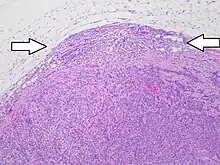

Lymph node metastasis is the spread (metastasis) of cancer cells into a lymph node.

Generally, metastases form first in the lymph nodes that are closest to the primary tumor. This is because the lymphatic fluid (lymph) of the cancerous organ or tissue flows first to these nearby lymph nodes. The tumor cells reach the lymph nodes via this lymphatic pathway, where they remain and proliferate. These spreading cancer cells grow in the lymph nodes, which causes the affected lymph nodes to get bigger.